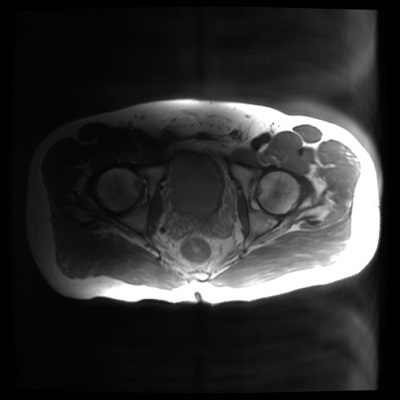

Figure 1. 1.5T Knee image acquired with 2D FSE on left and MAVRIC SL on right